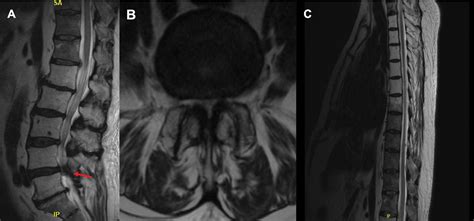

If you suspect you have this condition, a physician will typically perform a physical examination to test your range of motion and identify areas of tenderness. To confirm a diagnosis of Bilateral Facet Hypertrophy, imaging studies are essential.

MRI Offers detailed views of soft tissues, helping to see if the hypertrophic joints are compressing nerves or the spinal cord.